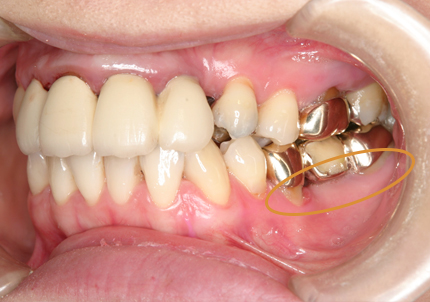

1.初診時口腔内(2007年6月30日)

2.右側上顎洞サイナスリフト後にインプラント埋入

↑ サイナスリフト術後

3.右上インプラント補綴物装着(2009年7月24日)

↑ 右上サイナスリフト後にインプラント埋入